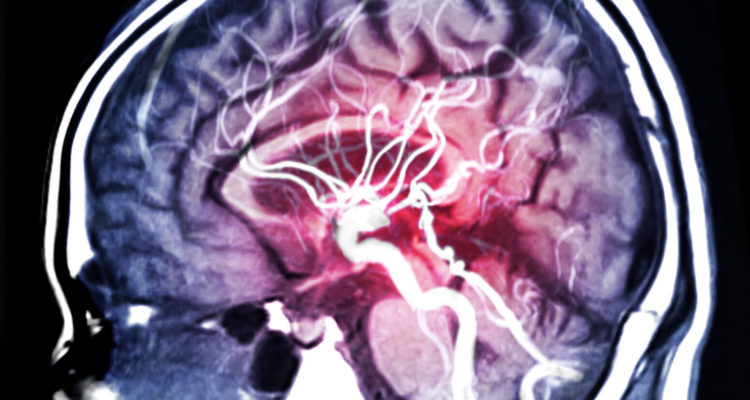

Терапевт зі Сполученого Королівства виступила в ЗМІ з поясненнями про ті неочевидні ознаки, якими може проявлятися інсульт. Також Рейчел Уорд нагадала про “класичні” ознаки цього небезпечного захворювання мозку: до них відносяться лицьова асиметрія, нездатність одночасно підняти обидві руки, нечленороздільна мова, оніміння частин тіла.

Говорячи про можливі неочевидні ознаки інсульту мозку, терапевт порадила не випускати з уваги наступні стани.

Гикавка. Відомі випадки, коли напередодні інсульту пацієнти гикали протягом доби або довше. Таке можливо через переривання згустком крові нормального кровопостачання задньої частини мозкового стовбура.

Головний біль. При інсульті вона стає толерантною до дії анальгетиків.

“Якщо голова немов розколюється, а таблетки ніяк не допомагають, викликайте швидку”, – порадила Рейчел Уорд.

“Чуже” тіло. Постраждала людина стає незграбною, тіло “відмовляється” підкорятися, виникають некеровані рухи – все це результат порушення в роботі мозкових центрів рівноваги.

Нудота. Вона може бути дуже сильною, супроводжуватися запамороченням.

Затуманений зір. Раптово зір перестає бути чітким, картинка в очах “розмивається”.